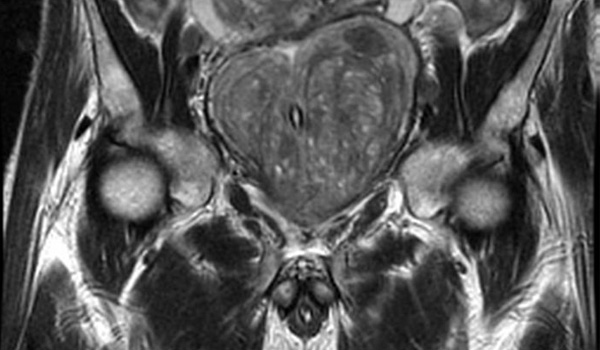

Los resultados de esta revisión sistemática y metanálisis sugieren que la integración de la resonancia magnética en las vías de detección del cáncer de próstata se asocia con un número reducido de biopsias innecesarias y un sobrediagnóstico de cáncer de próstata insignificante, al tiempo que se mantiene la detección de cáncer de próstata clínicamente significativo en comparación con la detección solo con PSA. JAMA Oncol, 5 de abril de 2024

Imágenes por resonancia magnética en los exámenes de detección del cáncer de próstata: una revisión sistemática y metanálisis

Los resultados de esta revisión sistemática y metanálisis indican que la integración de la resonancia magnética (RM) en las vías de cribado del cáncer de próstata (CaP) se asocia con un número reducido de biopsias innecesarias y un sobrediagnóstico del CaP insignificante, al tiempo que se mantiene la detección de CaP clínicamente significativos (csPCa) en comparación con el cribado solo del PSA. JAMA Oncol 5 de abril de 2024